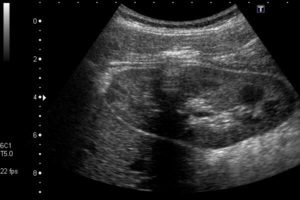

- УЗИ – уменьшение объема почек, толщины паренхимы (работающей ткани), при допплерографии обнаруживают замедленное внутрипочечное кровообращение.

Если выведение мочи затруднено камнями, то на ультразвуке будет соответствующая картина: увеличенная почка, наполненная жидкостью, которая отображается темной зоной на экране, а камни, отражающие звуковые волны, будут белыми. Подобным образом обнаруживаются и другие патологи, опухоли, киста — мешочки, наполненные жидкостью, которые увеличивают часть паренхимы почки в размерах.

Более плотные участки тканей (эхогенные образования) отражают больше звуковых волн, вызывая, тем самым, более сильное эхо. Такие области видны на карте эхограммы в виде ярких участков или пятен в темной области.

Темная область, отображаемая на экране, как правило, соответствует участку с низкой эхогенностью, которая, например, наполнена жидкостью.

Если при УЗИ почек было обнаружено в области лоханки несколько белых пятен, то сонолог скажет пациенту о найденных камнях в почках — микрокалькулезе.

Если на экране фиброзная капсула утолщена и неровная, то у врача будут подозрения на гломерулонефрит, для которого также характерна следующая картина: повышенная эхогенность органа, утолщение паренхимы и другие диффузные изменения ткани органа.